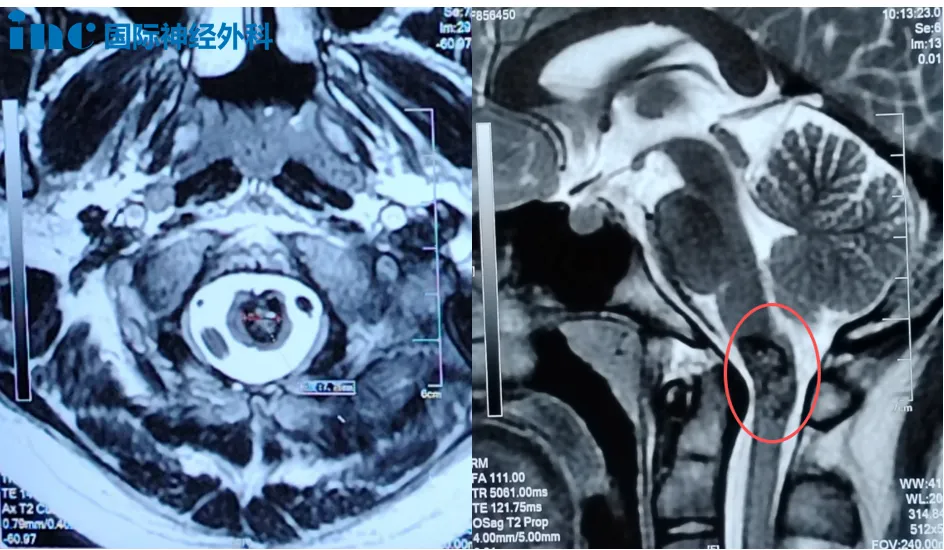

14歲男孩小宇,今年8月突然開始頭痛、嘔吐,手腳也陣陣發(fā)麻。頭顱核磁檢查提示,延髓異常信號(hào),考慮海綿狀血管瘤。這個(gè)聽起來有些陌生的病變,就長(zhǎng)在生命中樞所在的延髓與頸髓交界的要害位置。住院治療十天后,小宇的癥狀好轉(zhuǎn)。到了9月,所有不適都消失了,可復(fù)查的核磁仍提示:延頸交界處異常信號(hào),直徑約8mm。癥狀消失了,可病灶沒有消失。

在見到巴教授之前,小宇父母聽到最多的說法是:“這手術(shù)做完,孩子可能會(huì)坐輪椅,可能會(huì)癱。”延髓位于腦干下部,連接橋腦與頸髓,富含多個(gè)神經(jīng)核團(tuán),包括支配人體呼吸中樞的神經(jīng)核團(tuán)等。因此,除了運(yùn)動(dòng)功能受損的恐懼,許多延髓手術(shù)患者還不得不面對(duì)術(shù)后可能依賴氣管插管的現(xiàn)實(shí)。

面對(duì)這個(gè)家庭的不安,巴教授的回應(yīng)清晰而堅(jiān)定:手術(shù)有把握,且建議手術(shù)。雖然孩子目前沒有癥狀,但病灶位置危險(xiǎn),尺寸也已不小。“可以等,但等待,就意味著要承擔(dān)隨時(shí)可能出血的風(fēng)險(xiǎn)。”